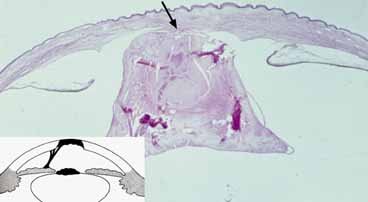

Fig. 23 Corneal staphyloma. A. Enucleated globe demonstrates marked ectasia of entire cornea. Cornea protruded between the eyelids at time of birth. B. Histopathology shows focal thinning of the cornea and vascularization with adherent shrunken lens. Clilary processes adhere to posterior lens. Atrophic iris (arrows) lines cornea and lens stalk (Hematoxylin-eosin, ×4). (Waring GO, Rodrigues MM, Laibson PR: Anterior chamber cleavage syndrome. Surv Ophthalmol 20:3–27, 1975)

Histopathologically, the epithelium shows central keratinization.136 There are also fragmented breaks in an attenuated Bowman's membrane. The corneal stroma is thin, disorganized, and vascularized. The endothelium and Descemet's membrane are absent and the posterior cornea is lined by atrophic iris tissue (Fig. 23B).136